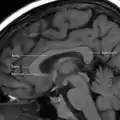

يسمى الجزء الخلفي من الجسم الثفني بالشريط؛ الجزء الأمامي يسمى الركبة؛ بين الجزئين ما يسمى بالجذع، أو "الجسم". غالباً الجزء بين الجذع والشريط ضيق بشكل ملحوظ وبالتالي يشار إليه ب "البرزخ". المنقار هو جزء من الجسم الثفني الذي يبرز للخلف وللأسفل من أكثر جزء أمامي للركبة، كما يمكن مشاهدته على الصورة السهمية للدماغ المعروضة على اليسار. المنقار سمي بذلك لأنه يشبه منقار الطائر. على كل جانب من الجسم الثفني، تنتشر الألياف في المادة البيضاء وتمر إلى مختلف أجزاء قشرة المخ؛ الألياف المنحنية للأمام من الركبة إلى الفص الأمامي تشكل الملقط الأمامي، والألياف المنحنية للخلف إلى الفص القذالي تشكل الملقط الخلفي. بين الملقط الأمامي والخلفي يكون الجزء الرئيسي من الألياف الذي يشكل البساط ويمتد جانبياً على الجهتين إلى الفص الصدغي، ويغطي الجزء الأوسط من البطين الجانبي. محاور عصبية رفيعة في الركبة تربط القشرة أمام الجبهية بين نصفي الدماغ؛ هذه الألياف تنبثق من حزمة من الألياف تشبه الشوكة من البساط، الملقط الأمامي. المحاور العصبية الأثخن في منتصف الجسم الثّفَني أو في جذع الجسم الثفني، تربط مناطق القشرة الحركية، وبتناسب الكثير من الجسم الثفني المكرس بشكل إضافي للمناطق الحركية بما في ذلك باحة بروكا. الجزء الخلفي من الجسم الثّفَني؛ المعروف بالشريط، ينقل معلومات حسية جسدية بين نصفي الفص الجداري والقشرة البصرية في الفص القذالي، هذه هي ألياف الملقط الأمامي.[2][3]

أجزاء الجسم الثفني بالرنين المغناطيسي